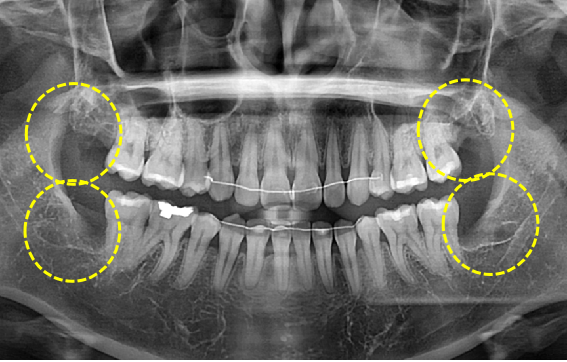

사랑니발치

Before

After